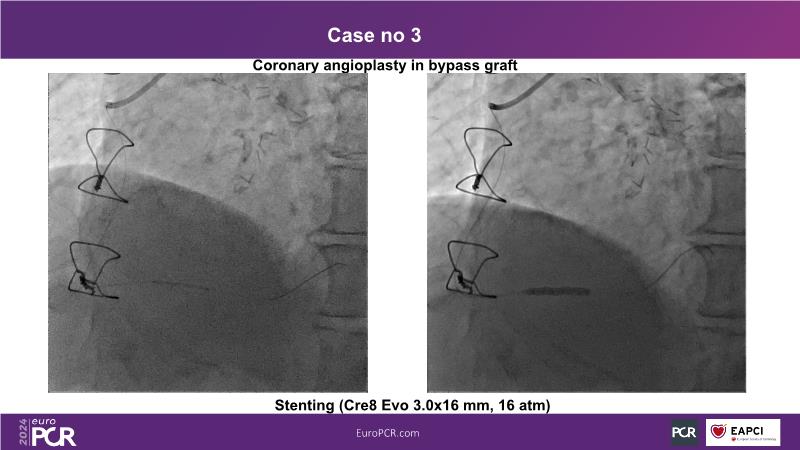

In this session, discover the effectiveness and safety of robotic PCI for both simple and complex lesions requiring additional devices like IVL, IVUS, laser, and FFR. Learn about the numerous benefits of robotics for patients and cathlab teams, including enhanced precision in wire navigation and stent positioning, full radioprotection, and reduced orthopedic injuries. Explore the growing interest in robotics within the interventional cardiology community, anticipate future technical advancements, and understand how AI will accelerate the integration of robotics and vice versa.